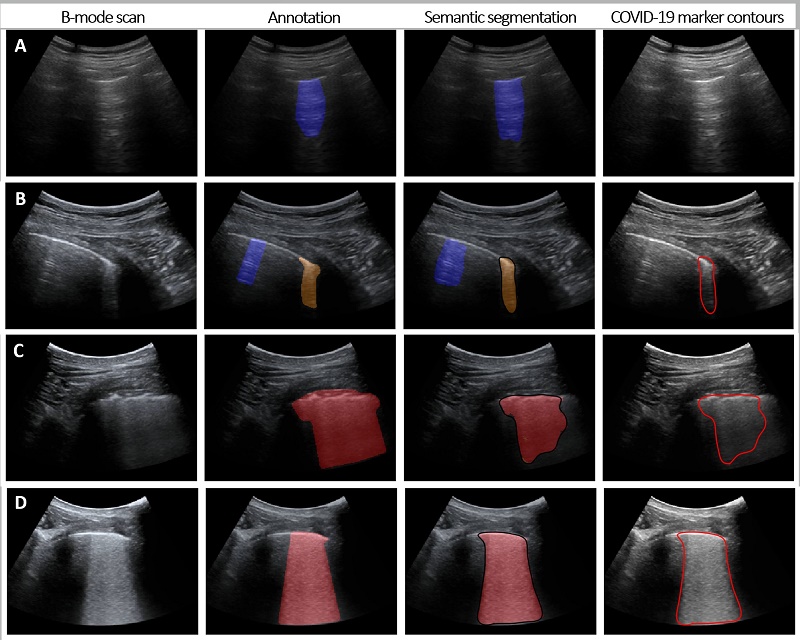

Column 1 and 2 show lung ultrasounds without and with annotated COVID-19 biomarkers (orange: moderate, red: severe). Columns 3 and 4 respectively show the semantic segmentations and contours of COVID-19 markers by means of deep learning analysis. Image: TU Eindhoven.

Ruud van Sloun, Assistant Professor and researcher at TU/e, worked day and night on this alongside four PhD students from Eindhoven: “With artificial intelligence, the most important biomarkers of severe lung diseases such as COVID-19 can be accurately determined on a lung ultrasound that visualizes the abnormalities at the edge of the lung and the changes in the structure of the network of pulmonary alveoli and interstitial tissue. And because it’s a program which learns, it becomes even smarter with each new use, allowing it to even more accurately determine whether or not the patient may have COVID-19. We’re very optimistic regarding its quick application in hospitals and emergency rooms.”